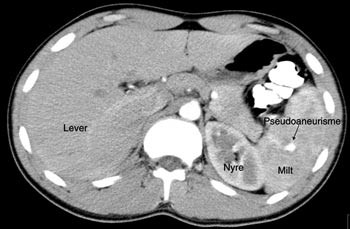

Pasient 1. En 16 år gammel gutt ble henvist til lokalsykehuset med spørsmål om miltskade. Han hadde seks dager tidligere falt under fotballtrening. Pasienten kom gående og klagde over magesmerter. CT-undersøkelse supplert med arteriell kontrastfase gav tydelig fremstilling av en rund, velavgrenset og høyattenuerende lesjon (fig 2a). På bildene fra vanlig venøs kontrastfase var denne strukturen dårligere fremstilt (fig 2b). Pseudoaneurisme ble mistenkt. Skaden ble vurdert som grad IV. Pasienten ble overflyttet til Ullevål universitetssykehus hvor det ble utført angiografi som bekreftet diagnosen. Deretter foretok man embolisering (fig 3). Prosedyren var vellykket og pasienten ble utskrevet etter én uke.